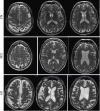

The scientists are dedicated to studying the detection of Alzheimer's disease onset to find a cure, or at the very least, medication that can slow the progression of the disease. This article explores the effectiveness of longitudinal data analysis, artificial intelligence, and machine learning approaches based on magnetic resonance imaging and positron emission tomography neuroimaging modalities for progression estimation and the detection of Alzheimer's disease onset. The significance of feature extraction in highly complex neuroimaging data, identification of vulnerable brain regions, and the determination of the threshold values for plaques, tangles, and neurodegeneration of these regions will extensively be evaluated. Developing automated methods to improve the aforementioned research areas would enable specialists to determine the progression of the disease and find the link between the biomarkers and more accurate detection of Alzheimer's disease onset.

Figures